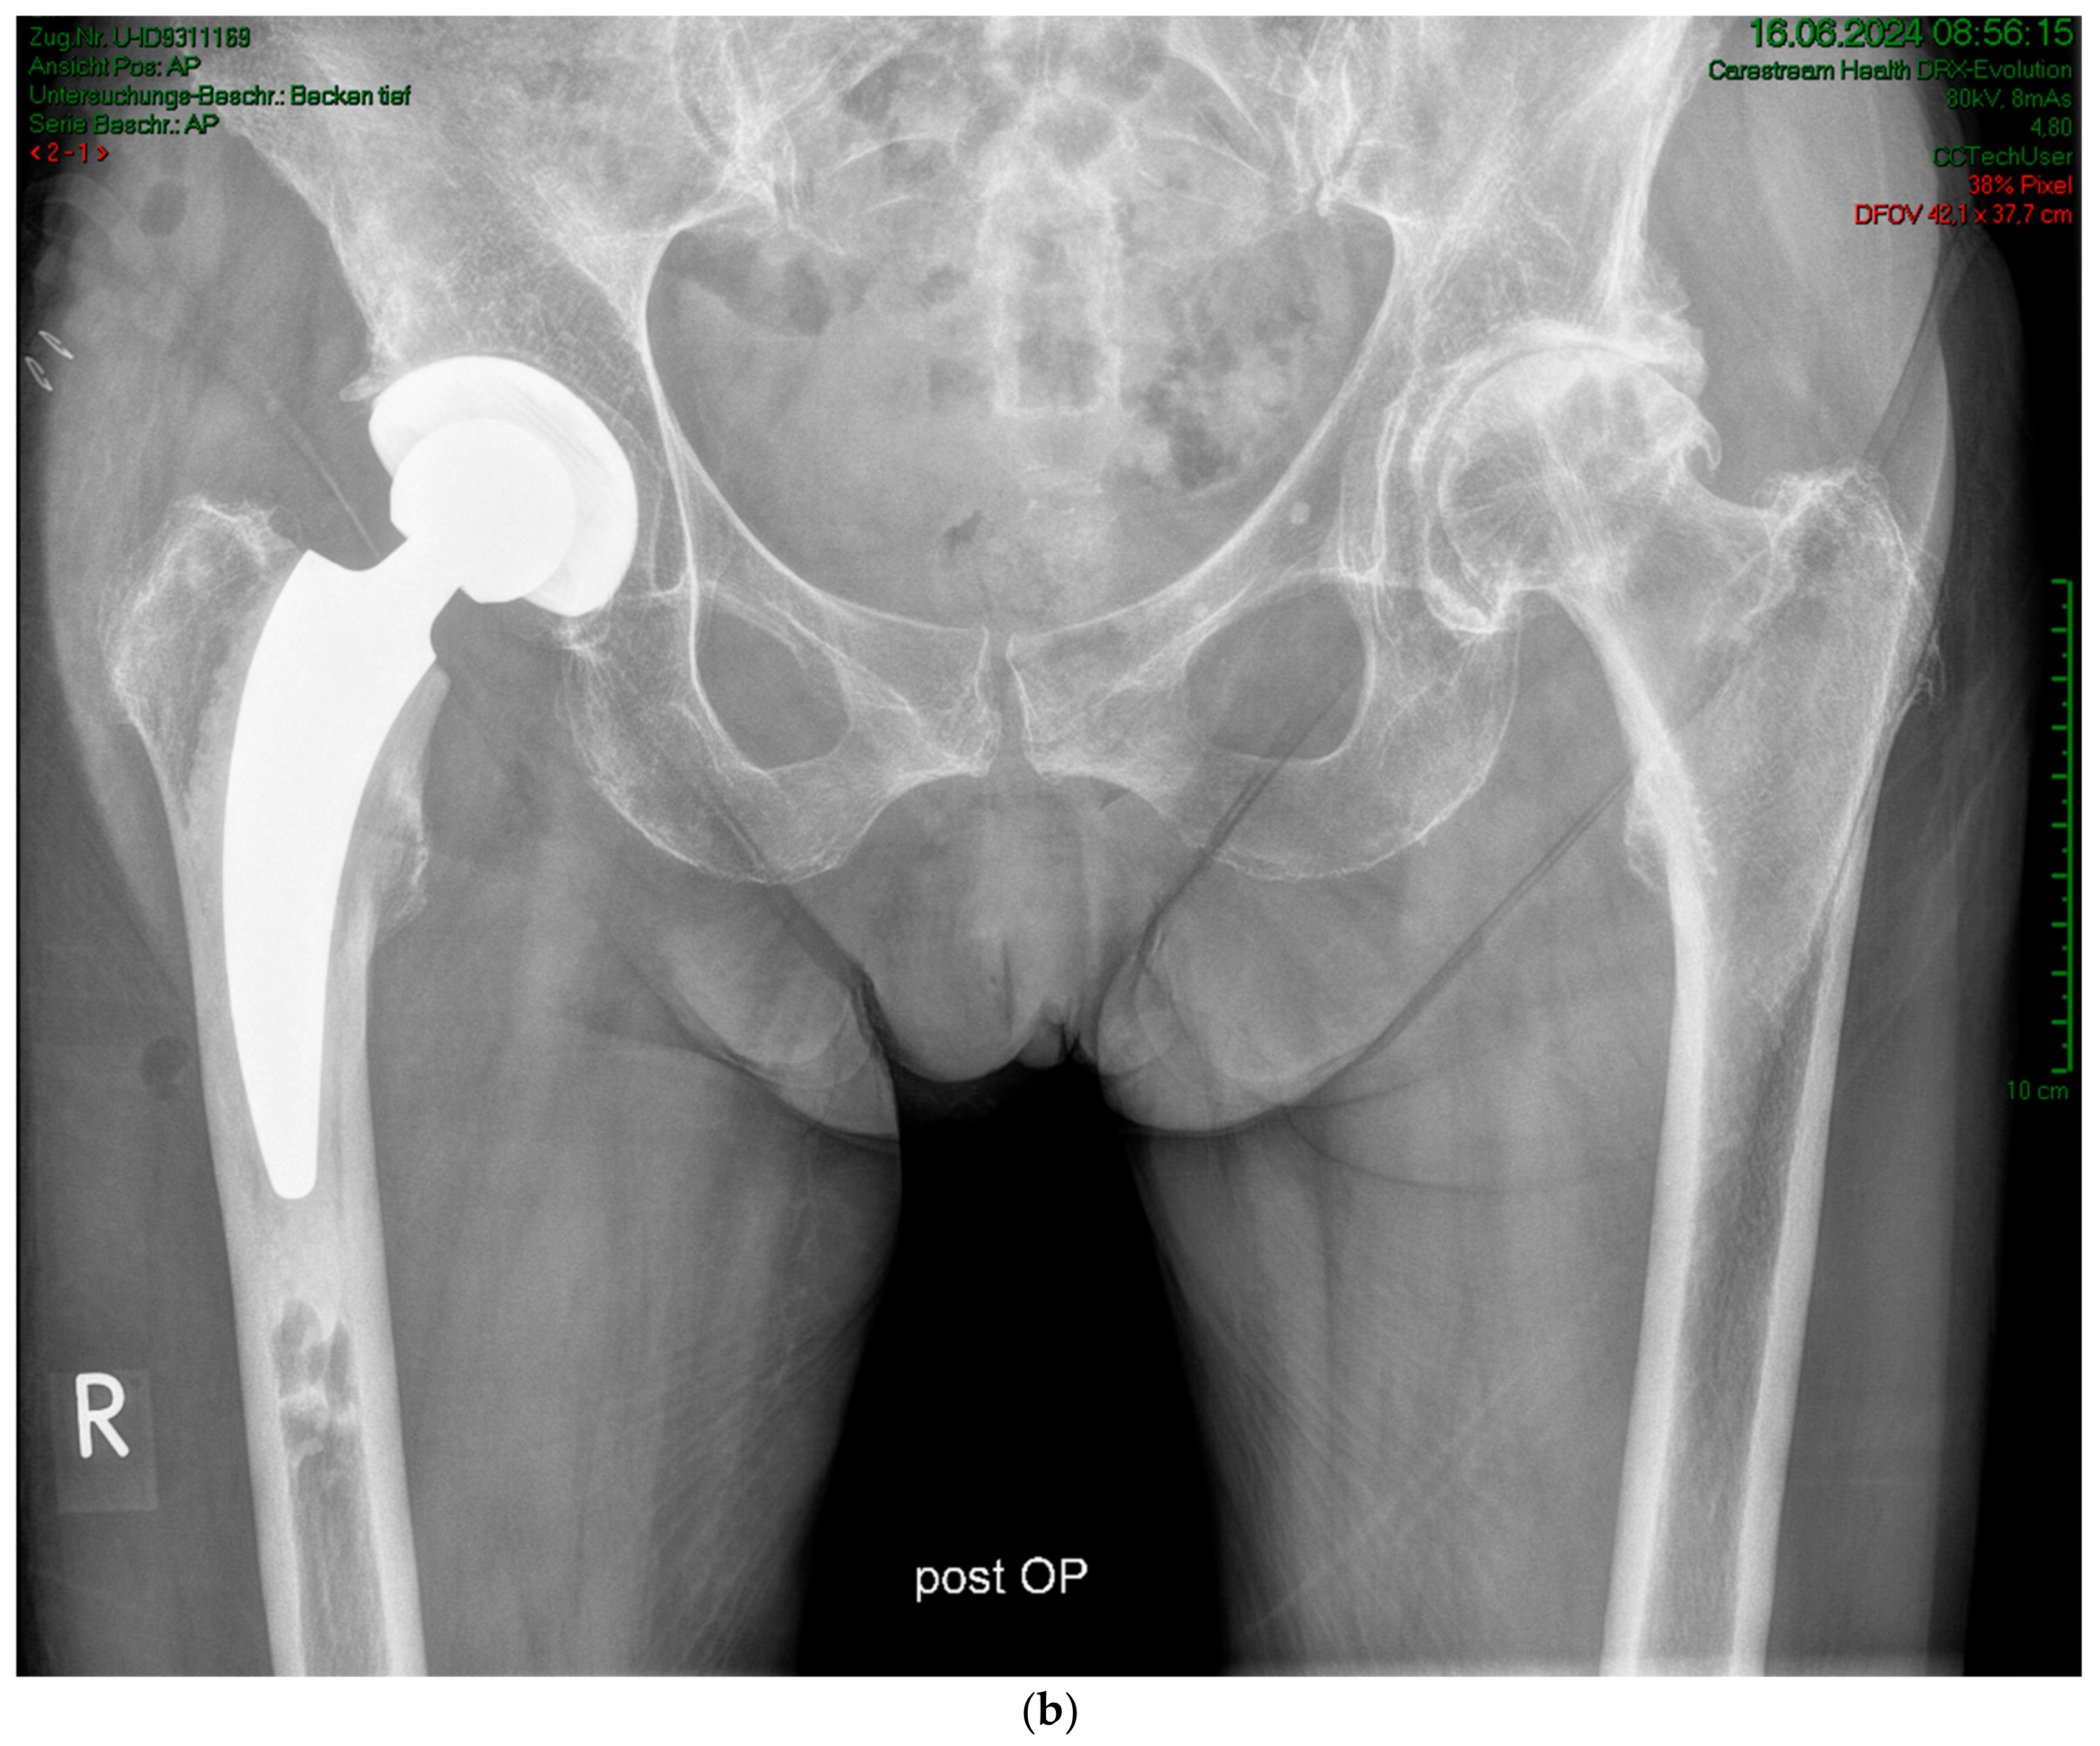

Figure 2.

Case #1: Female patient, 81 years old, with osteoporotic bone, coxa vara, and a Dorr C femur. (a) Preoperative planning for a cemented A2 stem combined with a cementless ANA.NOVA Alpha Cup. The image shows good reconstruction of the leg length and offset. (b,c) Postoperative anteroposterior (b) and axial (c) radiographic imaging 1 week postoperatively. Correct position of the stem and complete cement mantle.